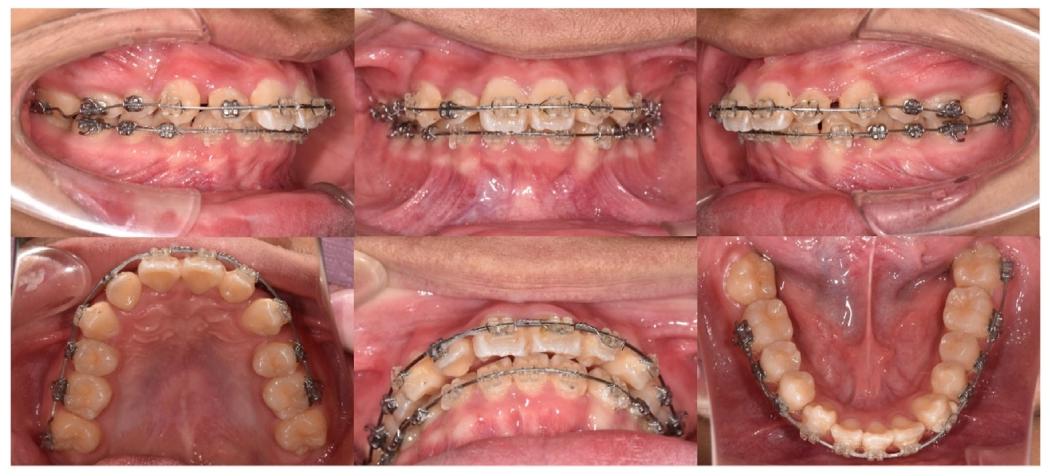

5. 精细调整与保持(22-40个月)

✅ 重新粘结中切牙托槽,调整覆合覆盖

✅ 拆除矫治器后,上颌戴用环绕式保持器,下颌Hawley保持器

第22月中切牙托槽调整